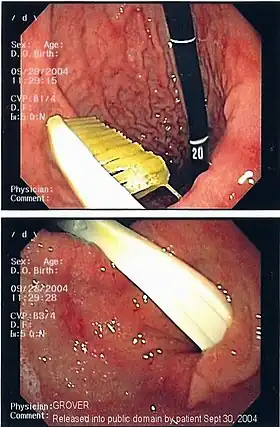

Commonly swallowed objects include coins, buttons, batteries, and small bones (such as fish bones),[1] but can include more complex objects, such as eyeglasses,[5] spoons,[6] and toothbrushes[5] (see image).

Endoscopic retrieval involves the use of a gastroscope or an optic fiber charge-coupled device camera. This instrument is shaped as a long tube, which is inserted through the mouth into the esophagus and stomach to identify the foreign body or bodies. This procedure is typically performed under conscious sedation. Many techniques have been described to remove foreign bodies from the stomach and esophagus. Usually the esophagus is protected with an overtube (a plastic tube of varying length), through which the gastroscope and retrieved objects are passed.[11]

Once the foreign body has been identified with the gastroscope, various devices can be passed through the gastroscope to grasp or manipulate the foreign body. Devices used include forceps, which come in varying shapes, sizes and grips,[12] snares, and oval loops that can be retracted from outside the gastroscope to lasso objects,[13] as well as Roth baskets (mesh nets that can be closed to trap small objects),[14] and magnets placed at the end of the scope or at the end of orogastric tubes.[12][15] Some techniques have been described that use foley catheters to trap objects, or use two snares to orient foreign bodies.[6]